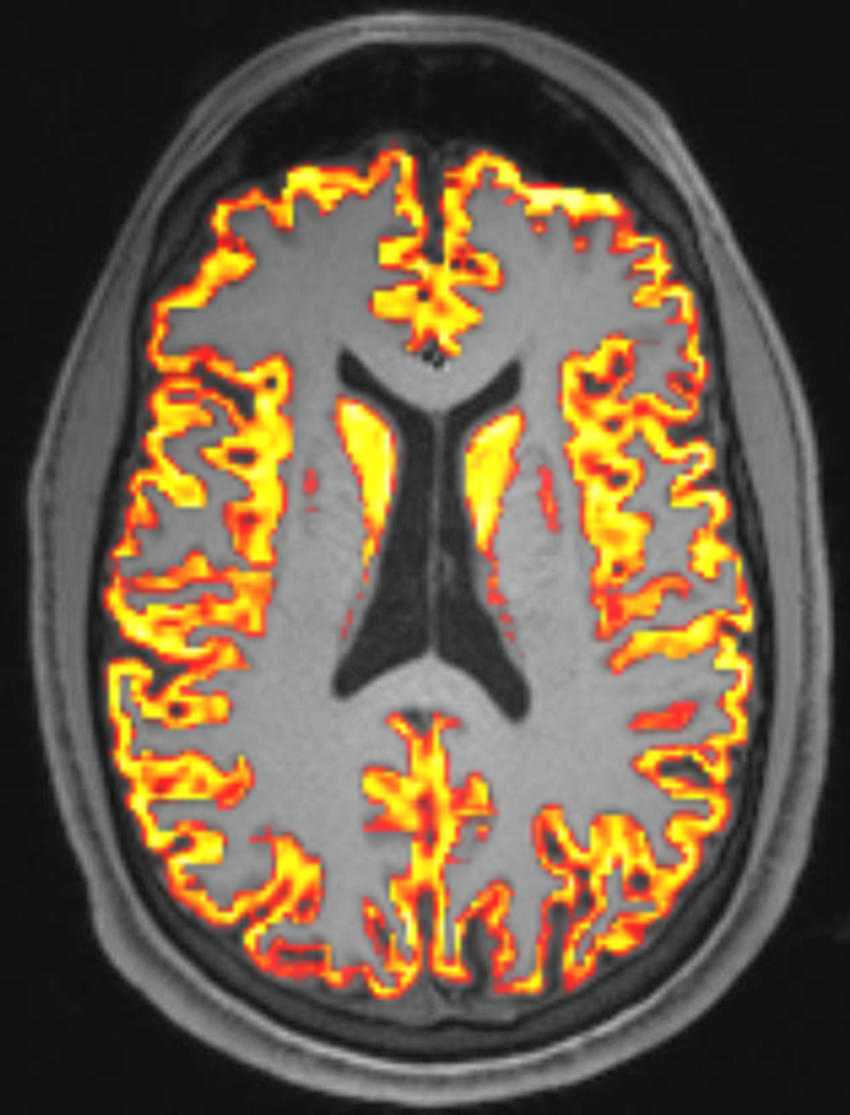

Figure 6. Example of brain MRI of a patient with long COVID

High-res (TIF) version

The results showed that lower pulmonary gas exchange may be associated with cognitive dysfunction, as well as lower gray matter and white matter volumes in patients with long COVID. In addition, the researchers observed significant relationships suggesting that increased cerebral blood flow is associated with decreased gas exchange in long COVID patients.

"This relationship could be a compensatory mechanism where lower lung function is compensated by higher cardiac output and higher brain perfusion," he said. "It's also a possibility that the disease mechanism that impairs pulmonary gas exchange also leads to higher brain perfusion through downstream vascular injury in both lung and brain."